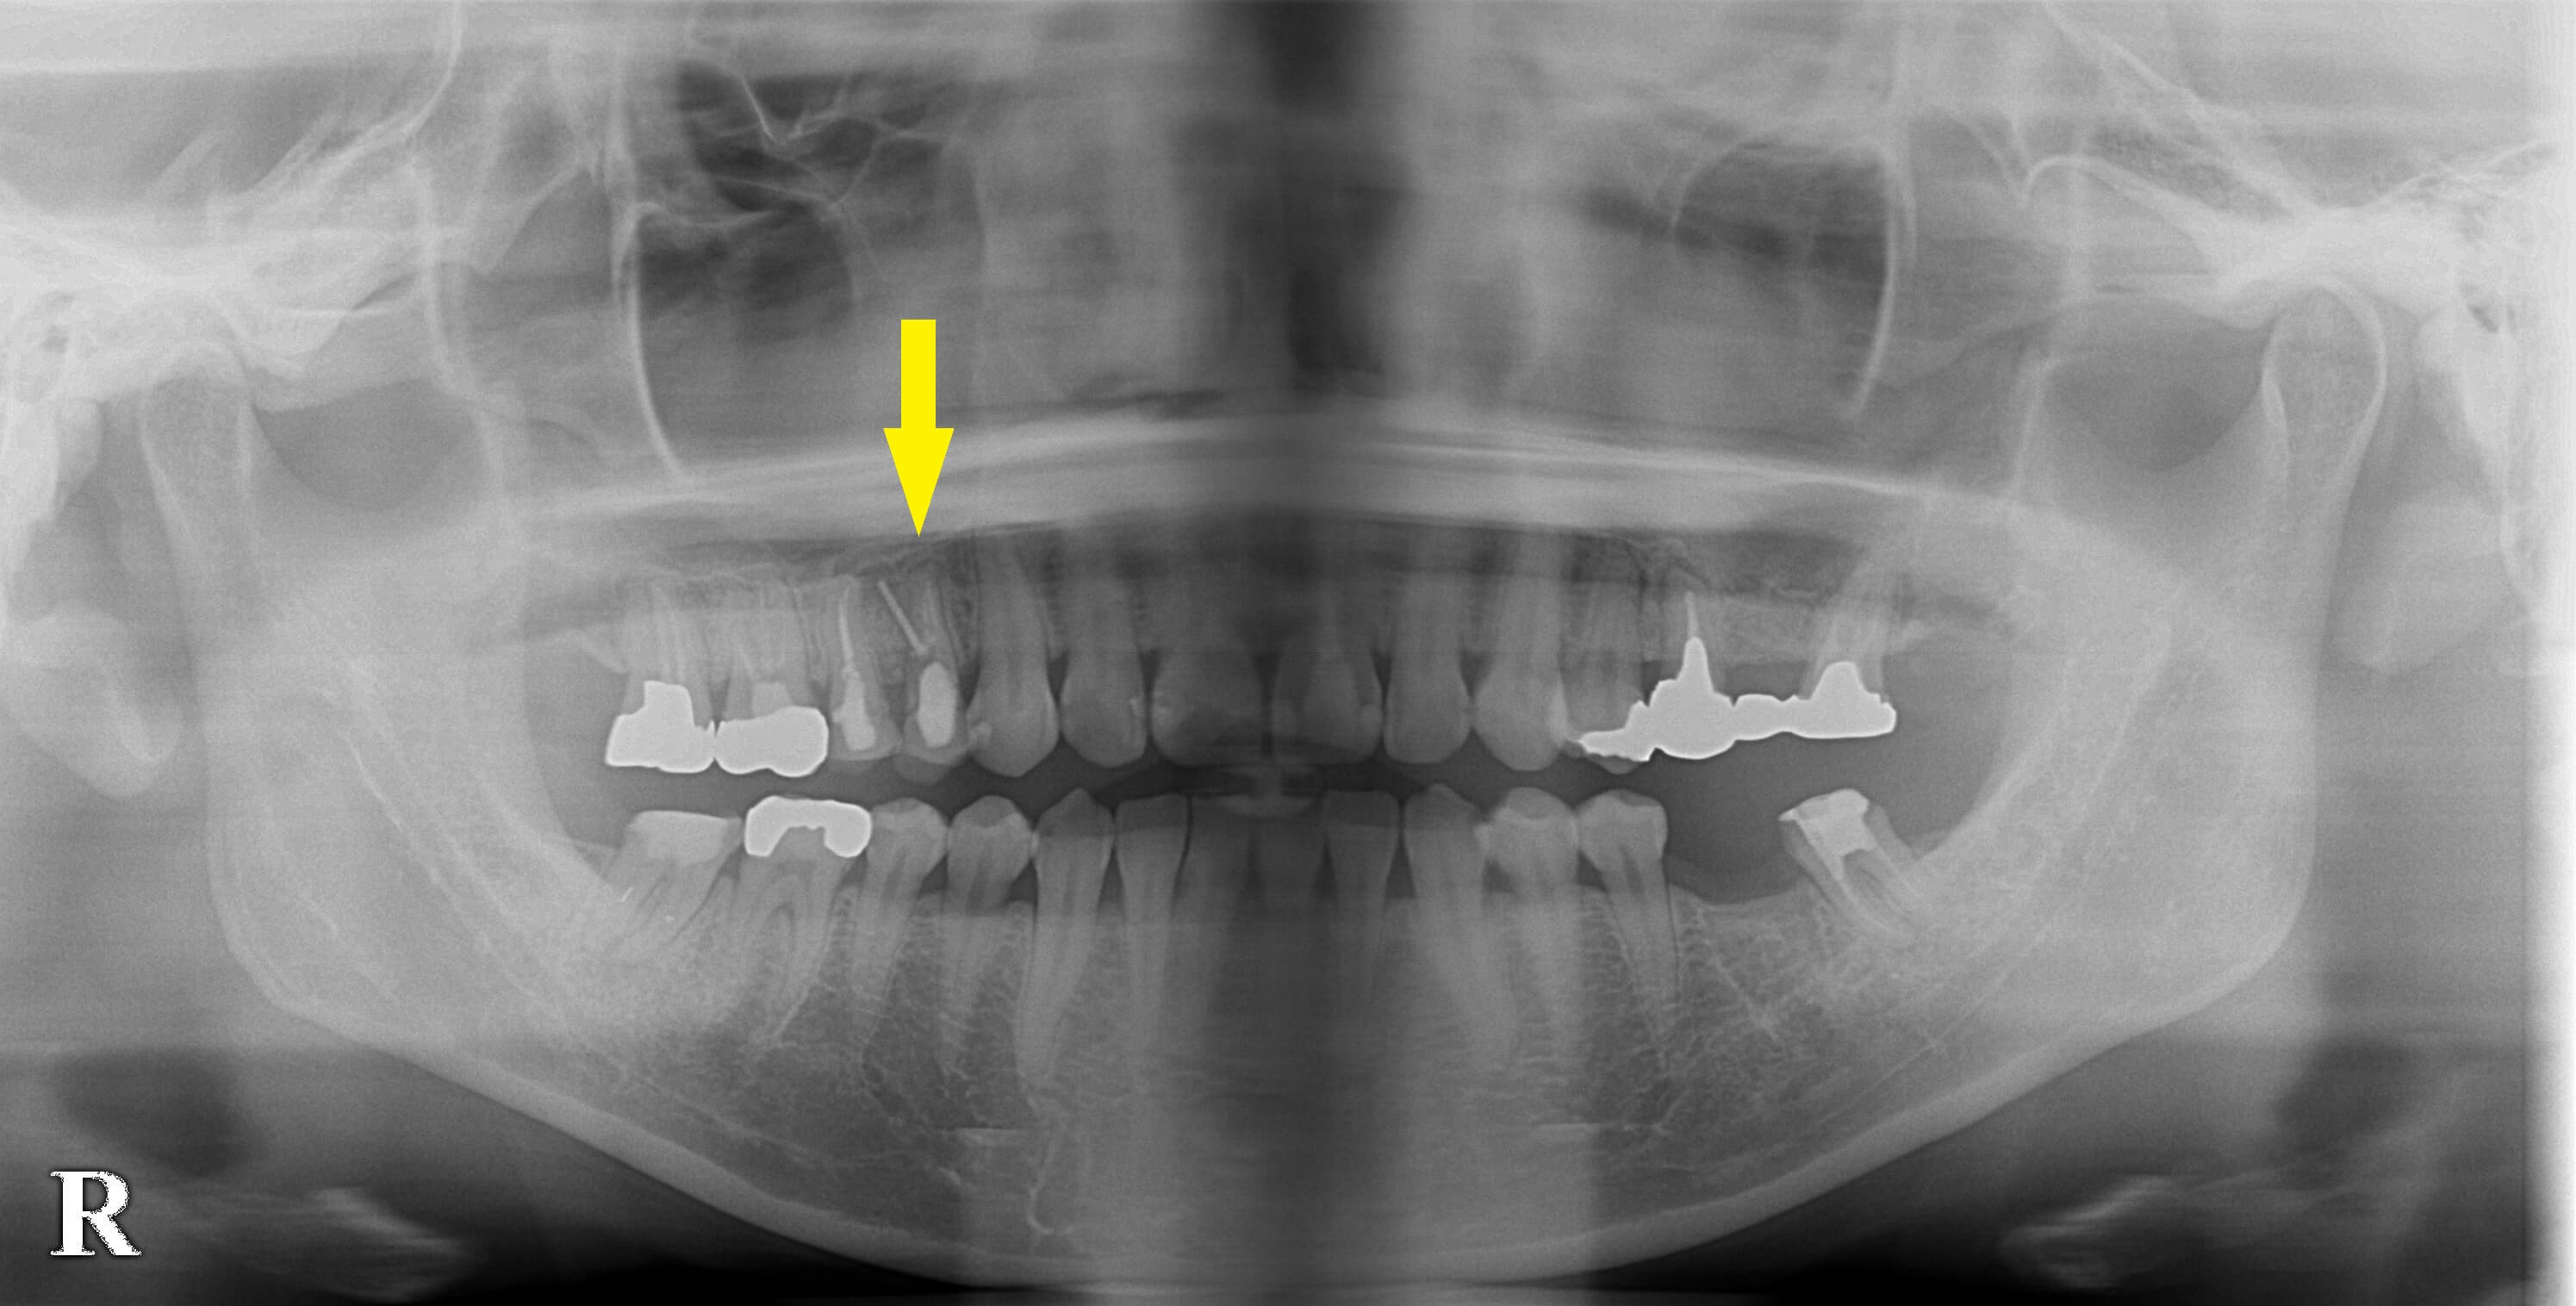

右上顎の小臼歯の歯根の状態が悪く、以前より腫脹、痛みを繰り返していたそうです。

神経を抜いて、歯根の治療をされているのですが、経過が不良で、抜歯した方が良いと言われたそうです。

治癒を待ってCTを撮影したところ、骨の高さが、少し不足していましたので、ソケットリフトという、骨造成を併用して、本日、インプラント埋入術を行いました。

下の写真2段目が手術前のCT、3段目が手術後のCTです。

インプラント体の上方に、骨補填材がドーム状に填入されているのが、お分かりいただけると思います。